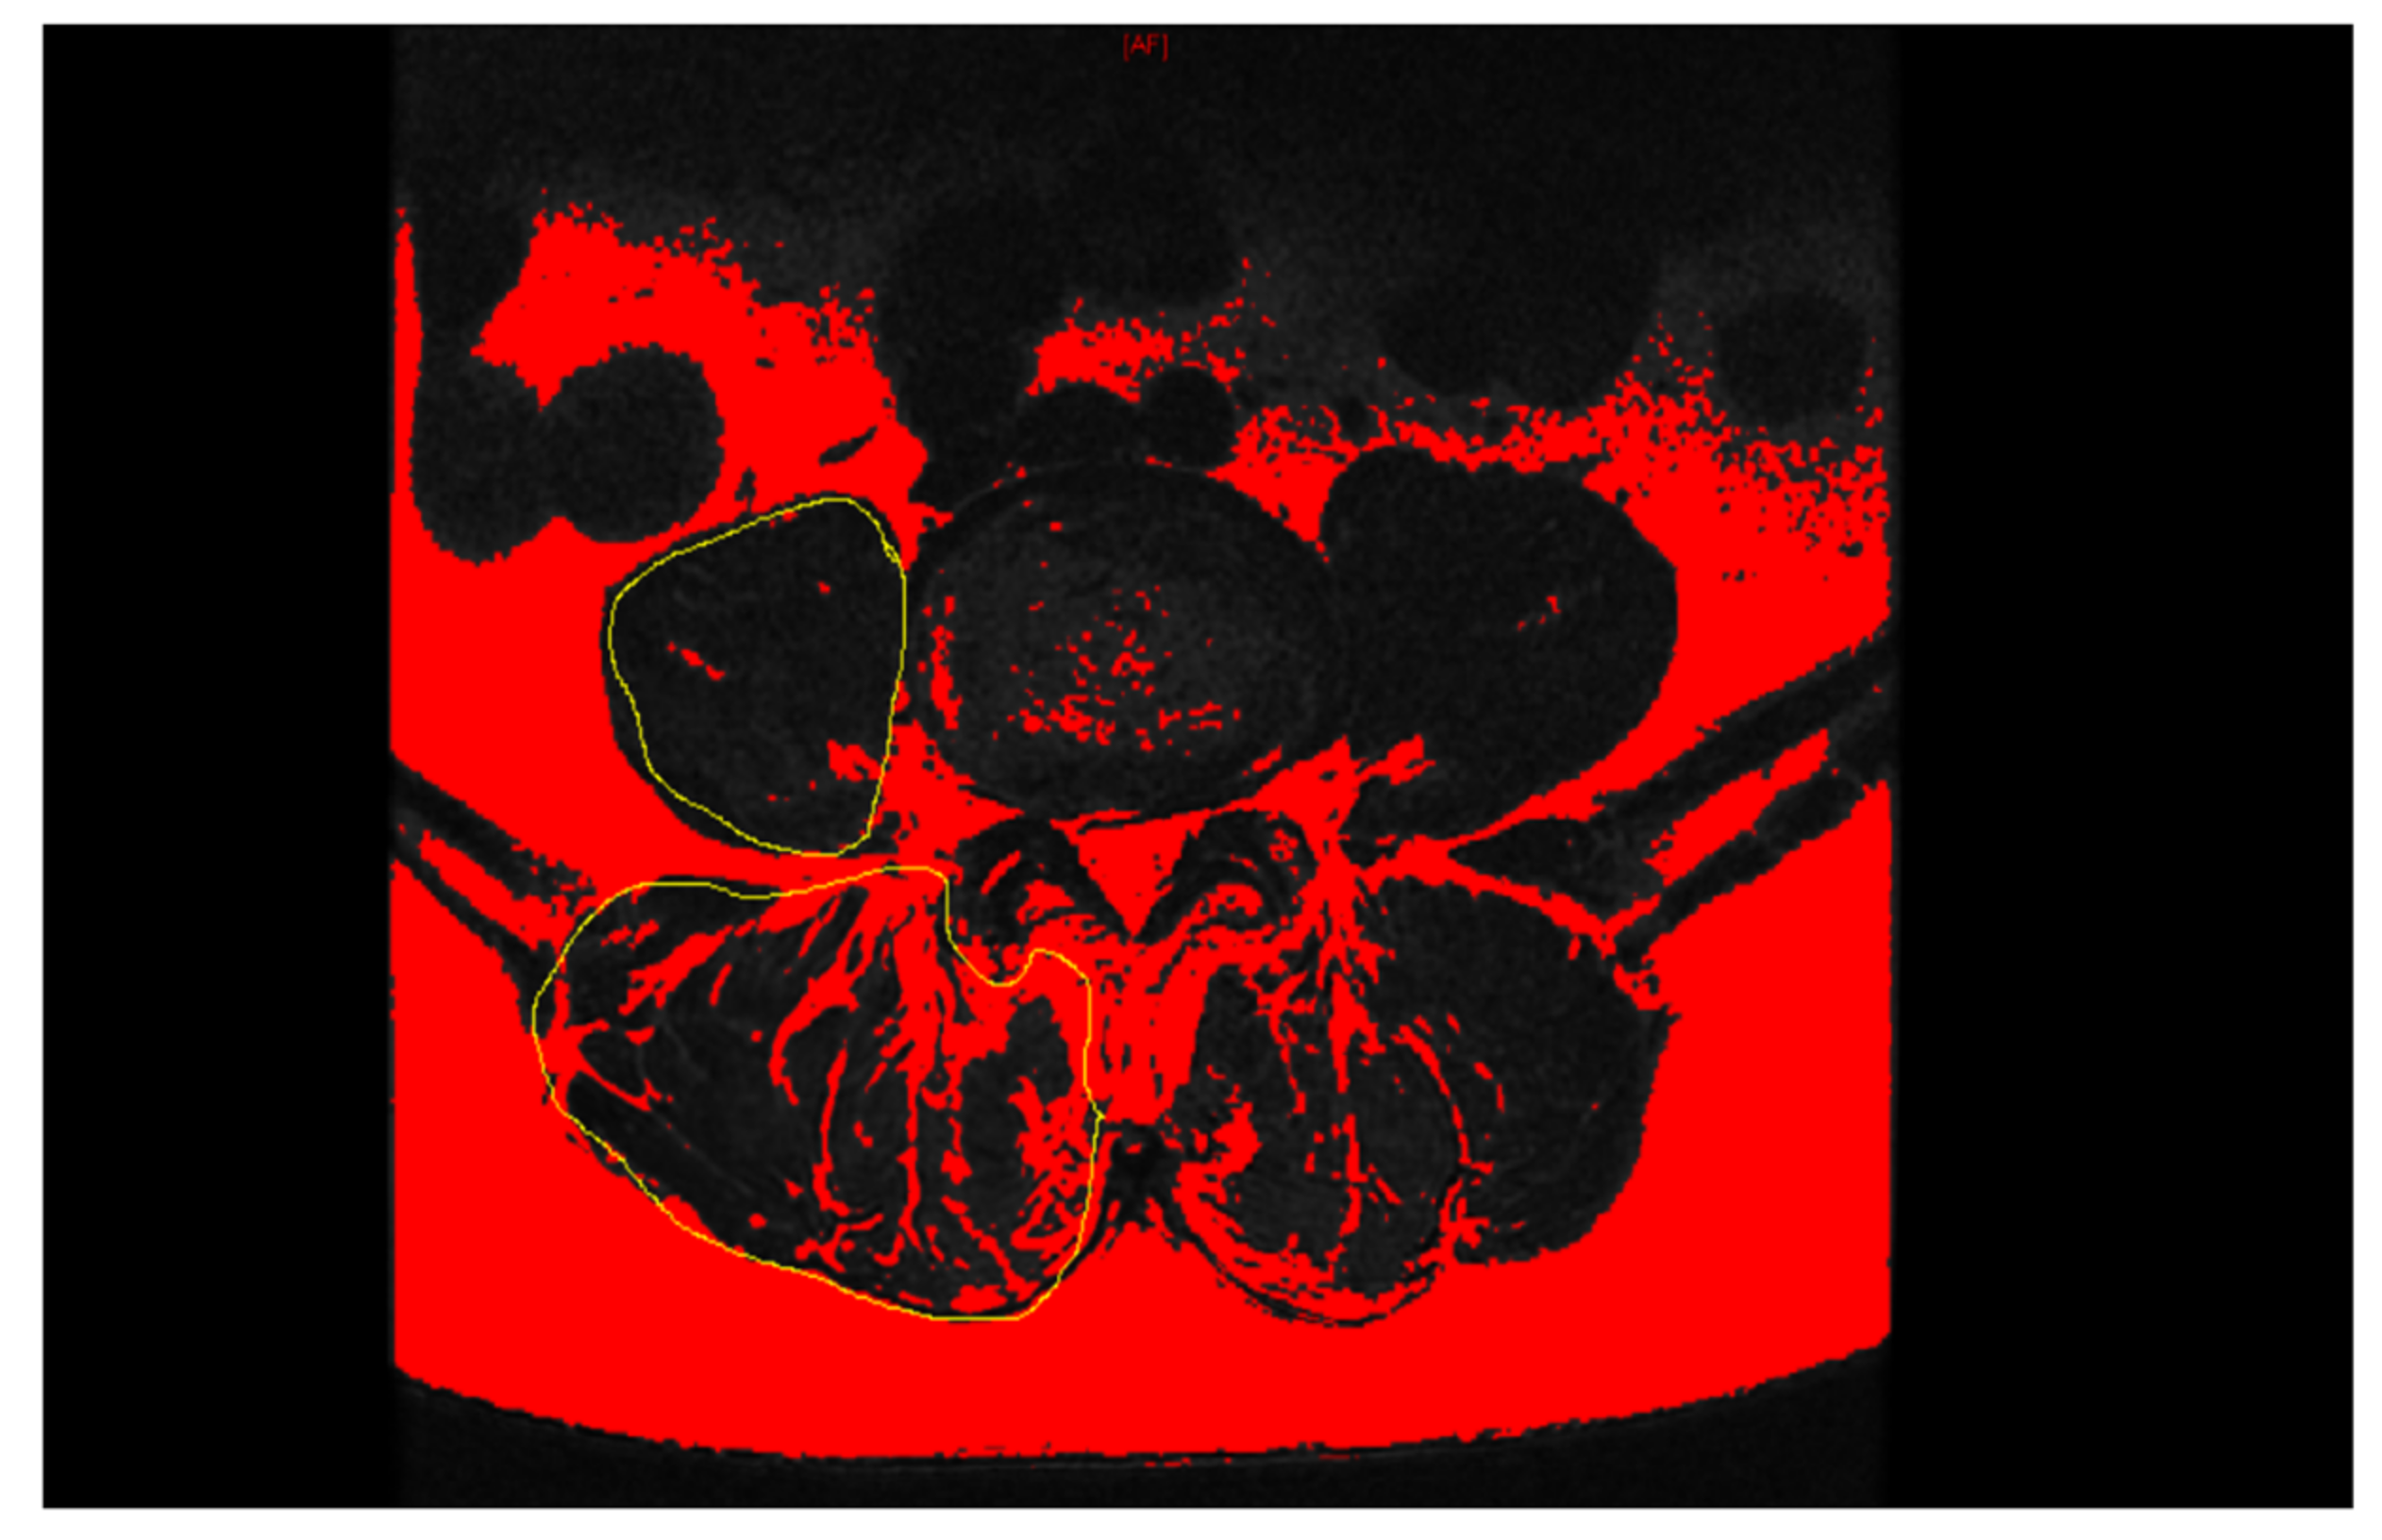

| Paraspinal muscle (L4-5) | |||||||

| PSM rCSA (%) | 150.05 ± 14.41 | 159.88 ± 23.41 | 159.20 ± 17.42 | 0.043 | 0.023 | 0.825 | 0.046 |

| PSM fatty degeneration (%) | 38.52 ± 12.41 | 32.33 ± 8.27 | 34.13 ± 8.23 | 0.028 | 0.020 | 0.213 | 0.008 |